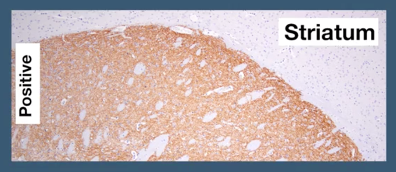

如果已知目的蛋白在一种组织类型中大量表达,但在其他组织中不表达,你可以将这些阳性和阴性组织的染色与您的实验样品进行比较。您应该对对照和实验样品使用相同的实验步骤和试剂,例如抗原修复缓冲液和抗体稀释剂。如果阳性和阴性对照都没有得出期待的结果,您应该对您的实验步骤和抗体工作浓度进行疑难排解,然后再处理您的实验样本。必须确认您没有使用过高浓度的抗体,因为这会造成非特异性结合,导致靶蛋白脱靶。

Adora2a (E518X) XP®️ #94871

阴性对照: